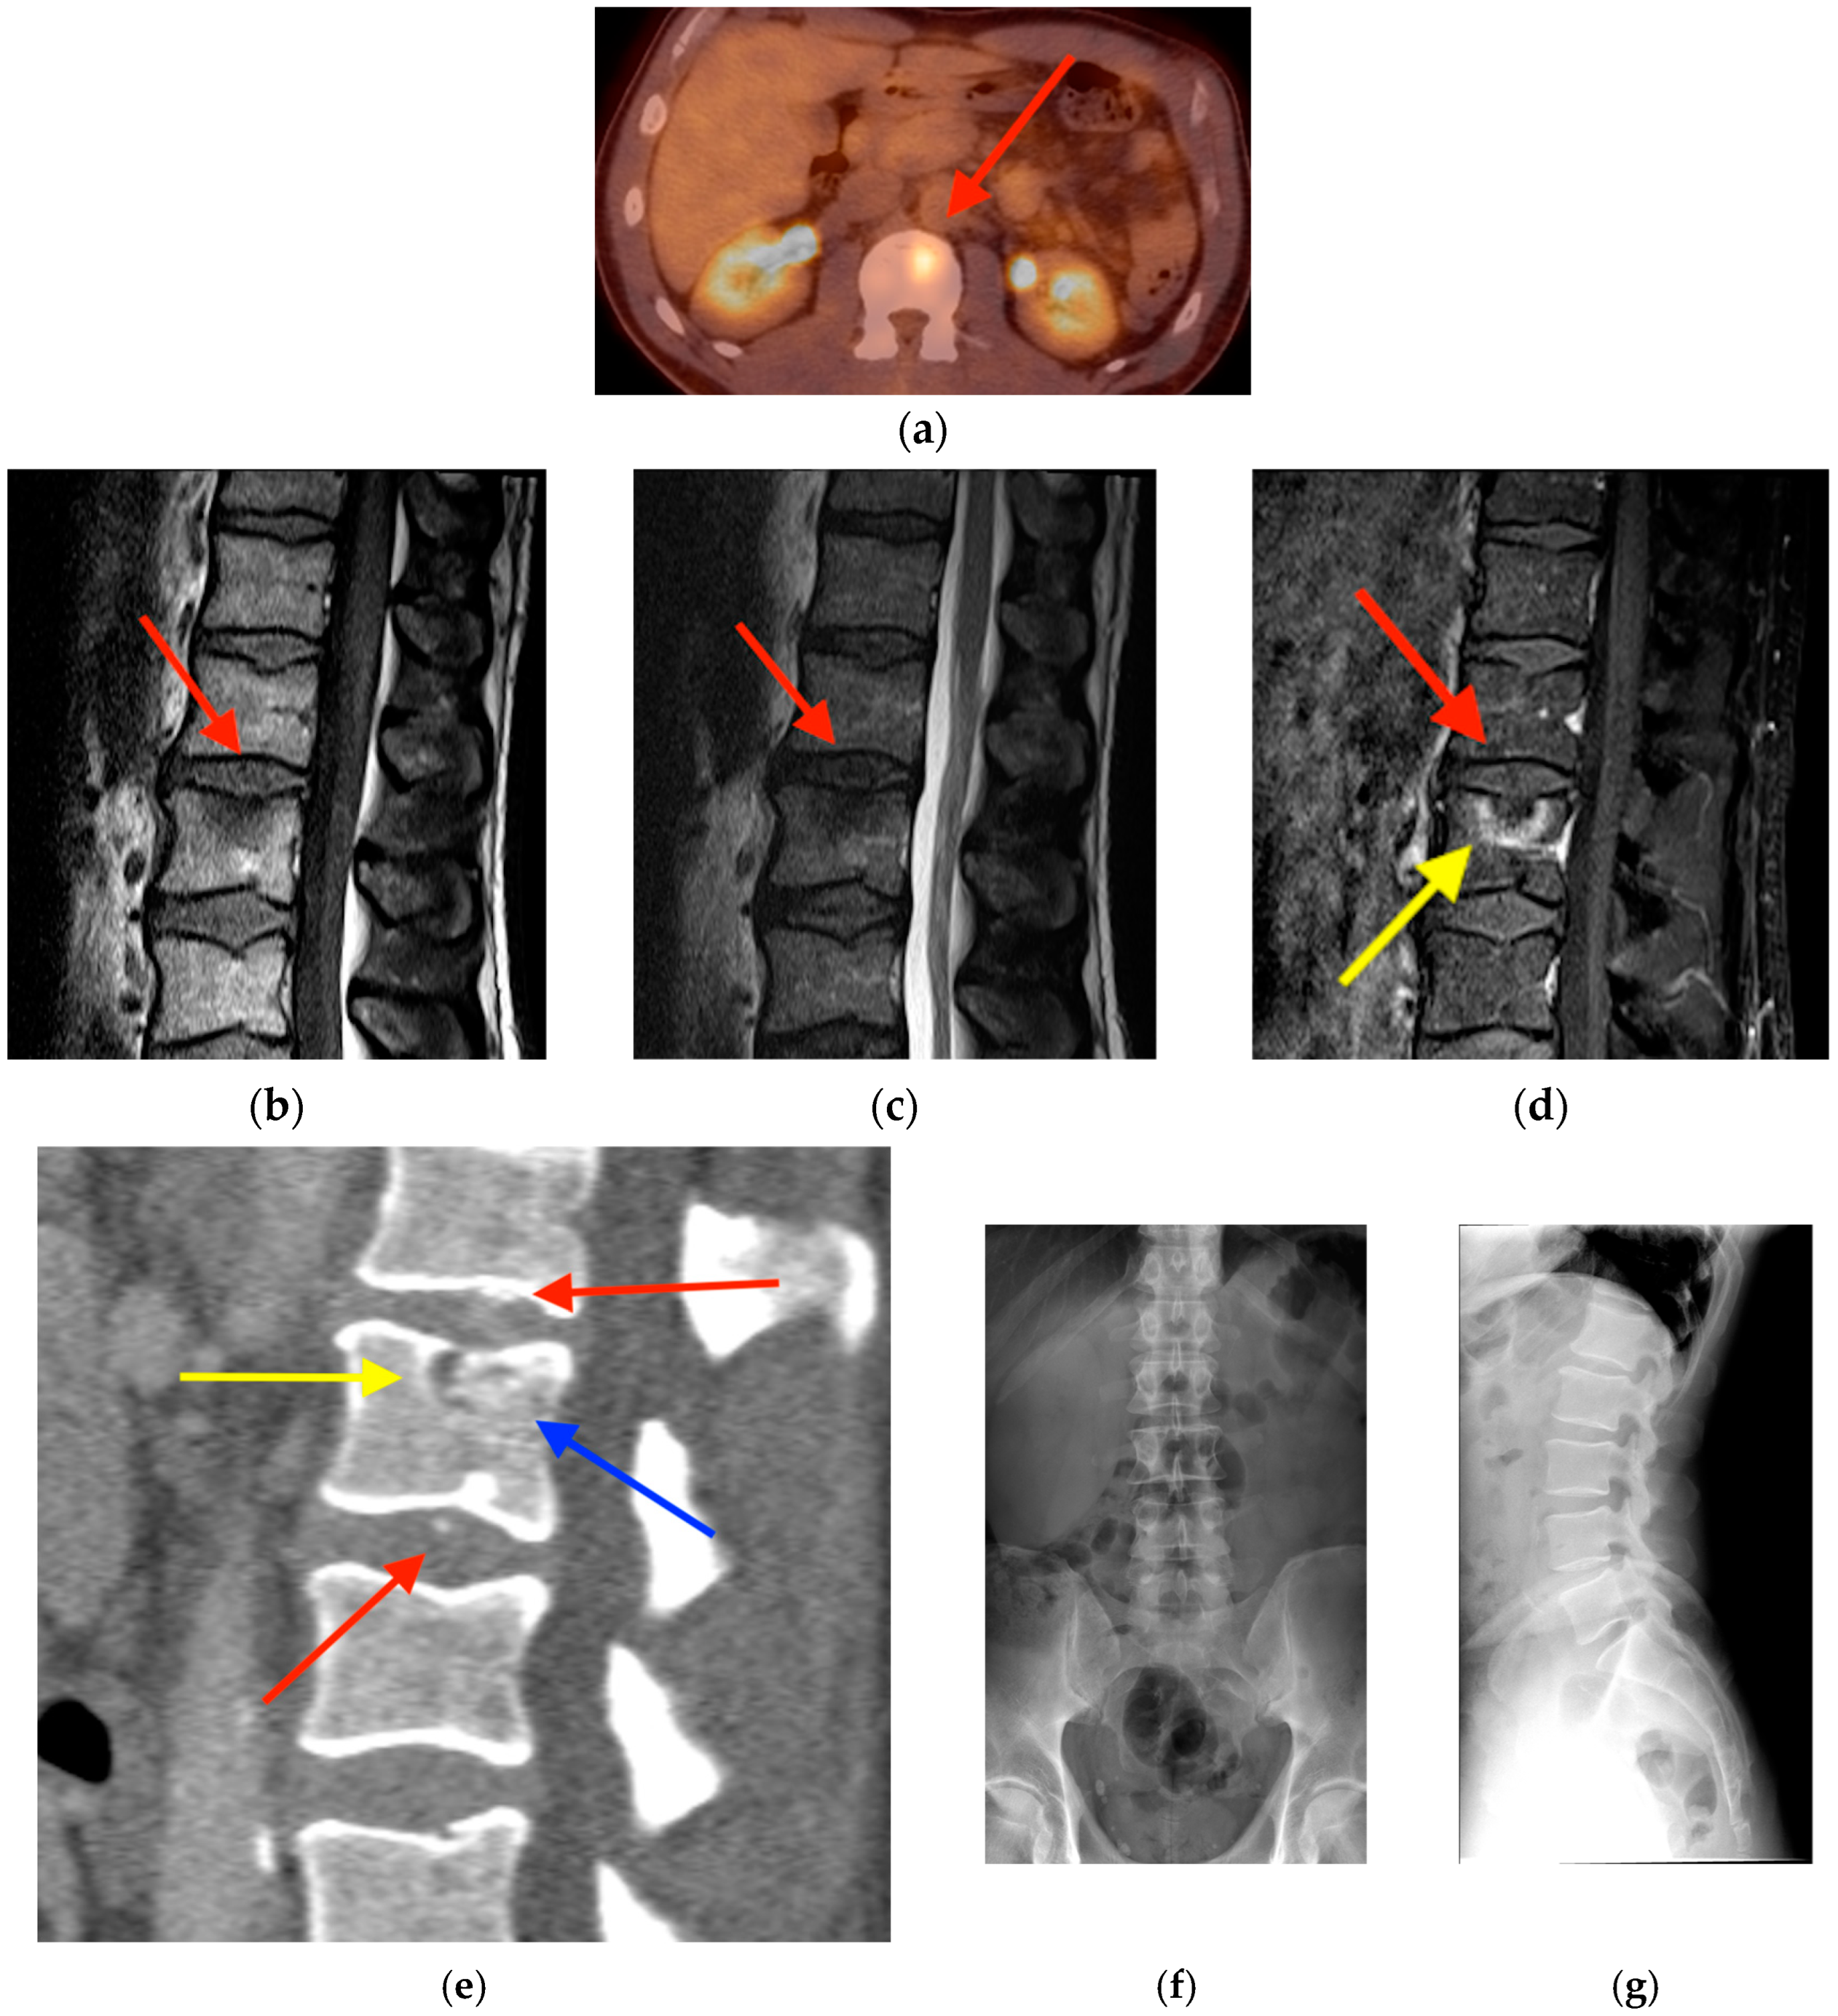

2.4. Schmorl’s Node

2.5. Vertebral Hemangioma